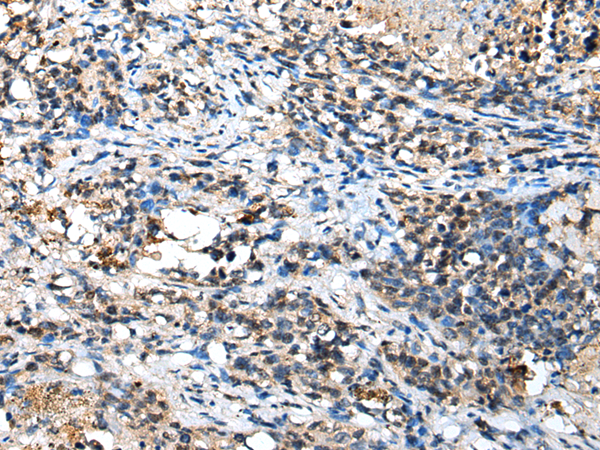

分类: 科研抗体货号: P09112别名: CFM2; FAM101A应用: IHC反应种属: Human